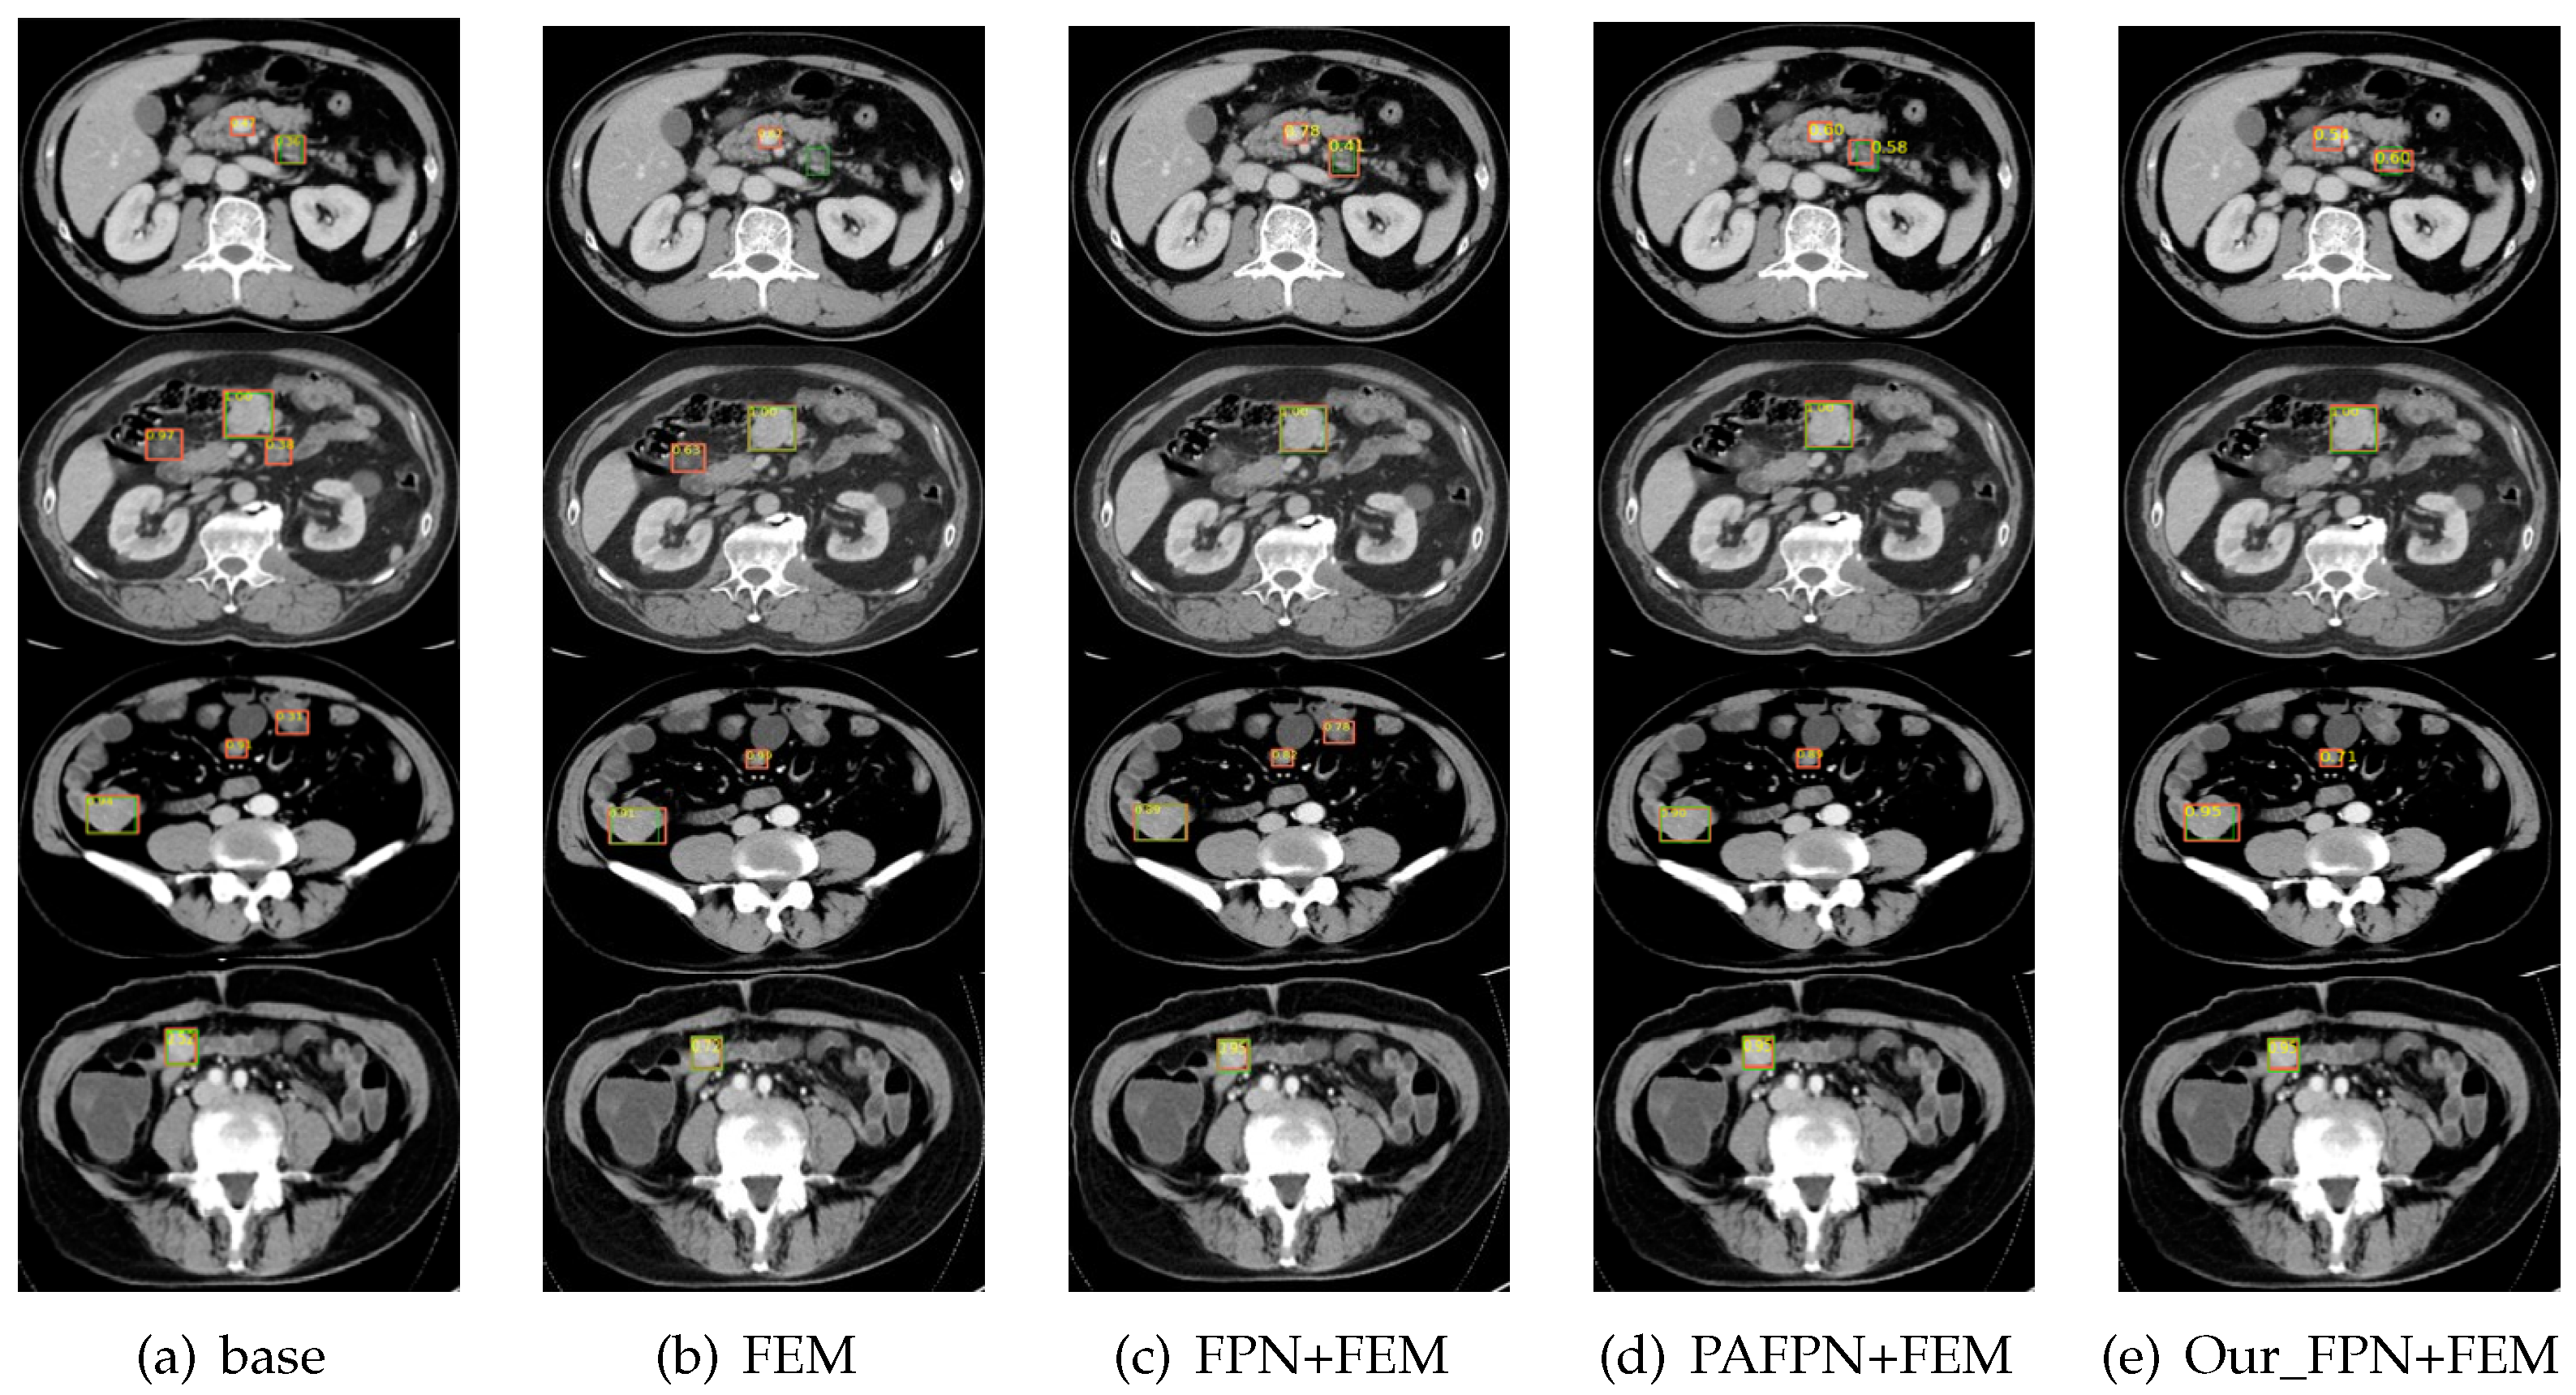

We respectively compare the effects of the Faster R-CNN without the multiscale module, with the initial FPN [27] module, with the PAFPN [33] module, and with the FPN module proposed in this paper, and the experimental results are shown in Table 3 and Figure 4. The data in the table show that the proposed FPN structure increases the AP of the entire item by 0.073, and the AP at all scales is improved by the improved FPN structure, with the most significant improvement for small objects. The suggested multiscale approach surpasses other methods in the AP of both the overall objects and each scale object, proving that the improved FPN is more effective for the task at hand.

As shown in Table 3 and Figure 5, we compared the test results using only the FEM, using the FPN module together with the FEM, using the PAFPN module together with the FEM, and using our FPN together with the FEM to verify the effectiveness of the FEM. As evident from the results in the table, the AP is slightly improved when using only the FEM without the multiscale module. Using FPN as the multiscale module, the FEM yields an AP improvement of 0.002, using PAFPN 0.004, and using the proposed multiscale module 0.04. Overall, the AP goes from 0.662 to 0.739 with the addition of the multiscale module and the FEM. Although the effect of the FEM on this task is not as significant as that of the multiscale module, a series of comparative experiments also proved that this module can improve the performance of the network.

Figure 4. Visual comparison of different feature pyramid networks (the orange bounding box in the figure represents the predicted box, and the green bounding box represents the actual labeled box).

Figure 5. Visual comparison of the FEM combined with the different feature pyramid networks (the orange bounding box in the figure represents the predicted box, and the green bounding box represents the actual labeled box).